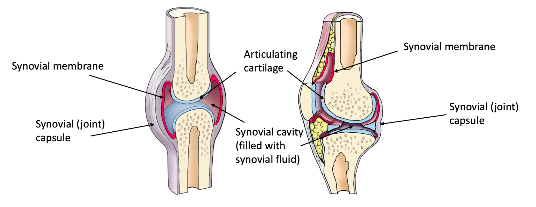

ligaments connect WHAT? [1]

role? [1]

what are articular discs aka?

role? [2]

ligaments connect bone to bone!!! [1]

role? [1]

stabilise and hold joint together

what are articular discs aka: menisci

role? [2]

maintain stability;

direct flow of synovial fluid towards areas of greatest friction